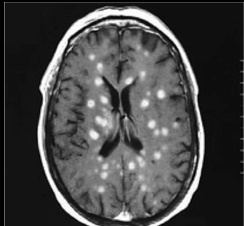

soap bubbles on head: Causes "soap bubble" lesions in gray matter

Neck brace: Can cause cryptococcosis, a fungal meningitis. Most common cause of fungal meningitis

vase with bubbling tar: India Ink test can diagnose Crypto meningitis with lumbar puncture/CSF. Background dark, transparent organism